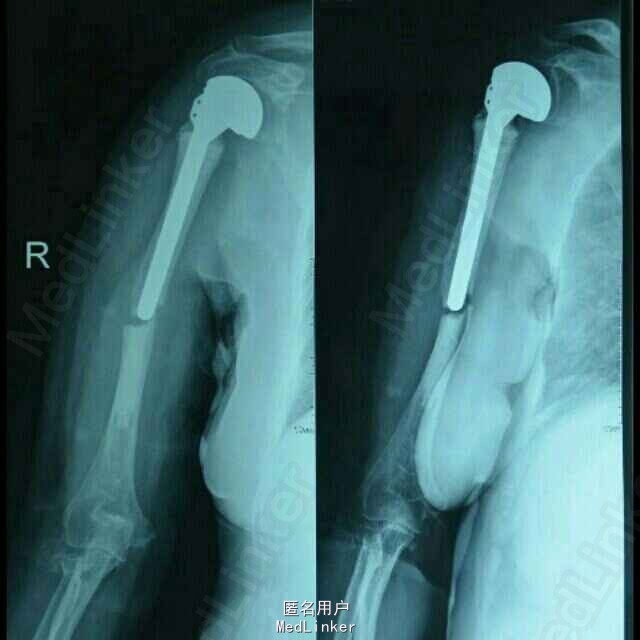

随访:术后1周指导患者功能锻炼,术后1月患肢功能基本恢复正常。讨论:患者系人工肩关节假体周围骨折,骨折远近段髓腔内填充有骨水泥,骨折端髓腔血运中断,故保守治疗效果欠佳,容易发生骨折多次移位,复位及固定困难,容易并发骨折延迟愈合,甚至不愈合,故应考虑积极手术治疗,早其有效固定骨折,并行局部植骨,有利于骨折生长及愈合;同时因患者右肱骨髓腔内骨水泥及金属假体填充,钻孔困难,钢板螺丝钉内固定术难度较大;同时不排除假体松动可能,故根据患者病情及具体情况,拟定手术方案:1、若假体松动,则行关节翻修,予更换加长柄假体,同时骨折部位记忆合金环抱器内固定;2、若术中假体无松动,则直接行“假体周围骨折切开复位记忆合金环抱器内固定术。